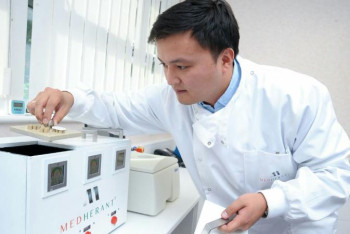

Отандық вакцина қайда өндіріліп жатыр?

Нұр-Сұлтан, BAQ.KZ тілшісі. Бұл туралы бүгін ҚР Президенті жанындағы Орталық коммуникациялар қызметі алаңында «Qazcovid-in қазақстандық вакцинасы туралы» тақырыбы аясында өткен онлайн брифинг кезінде Биологиялық қауіпсіздік проблемалары ғылыми-зерттеу институтының бас директоры Күнсұлу Закарья айтты.

Qazcovid-in вакцинасының бір дозасының құны қанша?

Нұр-Сұлтан, BAQ.KZ тілшісі. Бұл туралы бүгін ҚР Президенті жанындағы Орталық коммуникациялар қызметі алаңында «Qazcovid-in қазақстандық вакцинасы туралы» тақырыбы аясында өткен онлайн брифинг кезінде Биологиялық қауіпсіздік проблемалары ғылыми-зерттеу институтының бас директоры Күнсұлу Закарья айтты.

Qazcovid-in-нен бөлек тағы 4 вакцина өндірілуде

Нұр-Сұлтан, BAQ.KZ тілшісі. Бұл туралы бүгін ҚР Президенті жанындағы Орталық коммуникациялар қызметі алаңында «Qazcovid-in қазақстандық вакцинасы туралы» тақырыбы аясында өткен онлайн брифинг кезінде Биологиялық қауіпсіздік проблемалары ғылыми-зерттеу институтының бас директоры Күнсұлу Закарья айтты.

Қазақстандық ғалымдар КВИ-дің жаңа штамдарын зерттеп жатыр – Күнсұлу Закарья

Нұр-Сұлтан, BAQ.KZ тілшісі. Бұл туралы бүгін ҚР Президенті жанындағы Орталық коммуникациялар қызметі алаңында «Qazcovid-in қазақстандық вакцинасы туралы» тақырыбы аясында өткен онлайн брифинг кезінде Биологиялық қауіпсіздік проблемалары ғылыми-зерттеу институтының бас директоры Күнсұлу Закарья айтты.

Қазақстандықтар отандық вакцинаны сәуірдің соңында алады

Нұр-Сұлтан, BAQ.KZ тілшісі. Бұл туралы бүгін ҚР Президенті жанындағы Орталық коммуникациялар қызметі алаңында «Qazcovid-in қазақстандық вакцинасы туралы» тақырыбы аясында өткен онлайн брифинг кезінде Биологиялық қауіпсіздік проблемалары ғылыми-зерттеу институтының бас директоры Күнсұлу Закарья айтты.

Президент күтіп отырған отандық вакцина қашан дайын болады?

Нұр-Сұлтан, BAQ.KZ тілшісі. Бұл туралы бүгін ҚР Президенті жанындағы Орталық коммуникациялар қызметі алаңында «Qazcovid-in қазақстандық вакцинасы туралы» тақырыбы аясында өткен онлайн брифинг кезінде Биологиялық қауіпсіздік проблемалары ғылыми-зерттеу институтының бас директоры Күнсұлу Закарья айтты.

QazVac коронавирустың жаңа штамдарына қаншалықты қауқарлы?

Нұр-Сұлтан, BAQ.KZ тілшісі. Бұл туралы бүгін ҚР Президенті жанындағы Орталық коммуникациялар қызметі алаңында «Qazcovid-in қазақстандық вакцинасы туралы» тақырыбы аясында өткен онлайн брифинг кезінде Биологиялық қауіпсіздік проблемалары ғылыми-зерттеу институтының бас директоры Күнсұлу Закарья айтты.

Алдағы күндері «QazVас» дегенді жиі кездестіретін боласыздар – вице-министр

Нұр-Сұлтан, BAQ.KZ тілшісі. Бұл туралы бүгін ҚР Президенті жанындағы Орталық коммуникациялар қызметі алаңында «Qazcovid-in қазақстандық вакцинасы туралы» тақырыбы аясында өткен онлайн брифинг кезінде ҚР Білім және ғылым вице-министрі Мирас Дәуленов айтты.